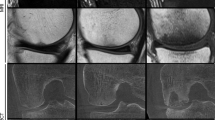

Cone-beam computed tomography (CBCT) has been being used in oral and maxillofacial fields forā>ā20Ā years, and it provides favorable visualization of details of small bony structures11. Compared with traditional or multidetector CT, it requires less space and provides higher spatial resolution under a possibly lower radiation dose exposure. Moreover, it is less invasive and more clinically accessible than MRI and BS. Therefore, using CBCT to diagnose scaphoid fractures is a promising strategy.

Recent studies on CBCT have shown that CBCT may replace conventional CT for scaphoid fracture diagnosis23,24. Practically, CBCT requires a relatively small space, which makes it easier for medical institutions to retrofit the new space. One of the main differences between CBCT and CT is that CBCT has a higher spatial resolution25,26,27, which makes it a more effective tool for bone visualization24. Moreover, CBCT is associated with a lower radiation dose than CT without optimizing the examination protocols28,29,30. Tschauner et al. found that adapted extremity CBCT imaging protocols can fall below optimized pediatric ankle and wrist CT doses at comparable image qualities31. Additionally, CBCT showed excellent agreement with CT to confirm fractures in patients with distal limb trauma32. Moreover, two studies have demonstrated that CBCT has high interrater agreement with CT for scaphoid fracture diagnosis13,15. Furthermore, Honigmann et al. indicated that CBCT is more cost-effective than CT and MRI33.